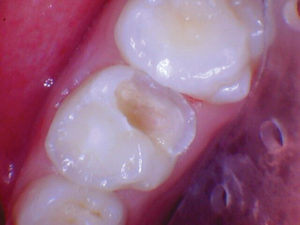

Figura 7. Después del ataque

con ácido y el uso del agente de unión Scotchbond Universal (3M), los dos

molares primarios superiores se restauraron con Activa Bioactive Restorative

A2. |